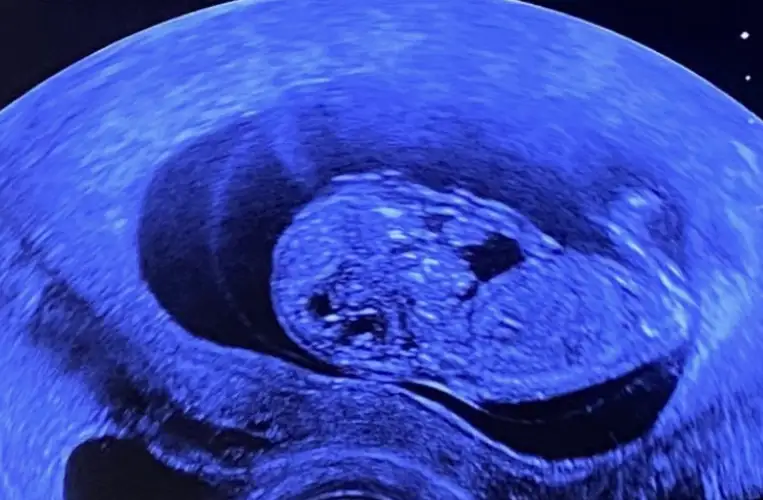

dr soylemeden siz gorun genital nub teorisi ( bebegin cinsiyeti)

Erkek ve kız için 11 yada 12 hafta usg görüntüsü olmalı açıklamalar asagıda yazıyor 😊 rabbim herkesin gönlüne göre nasip etsin inşallah .. ecmain

[/B]Eki Görüntüle 473828 gordugunuz gibi ust taraftaki simgedende anlasildigi gibi eger cikinti paralel ise kiz

yok 30°lik bir aciyla yukari dogru bakiyorsa %99 oglunuz olacak demektir simdi bi kac ornek resimler daha koyacagim kiziminkide dahil

yabancilarin hepsi biliyor bunu biz neden eksik kalalim gayet bilimsel simdi ellerinde11 12 13 ultrason fotografi olanlar alsin hemen baksin yada koyalim buraya yorumlayalim

Eki Görüntüle 473837 bu benim kizim cikinti gayet net ve ortada ve ben kizim diyooo